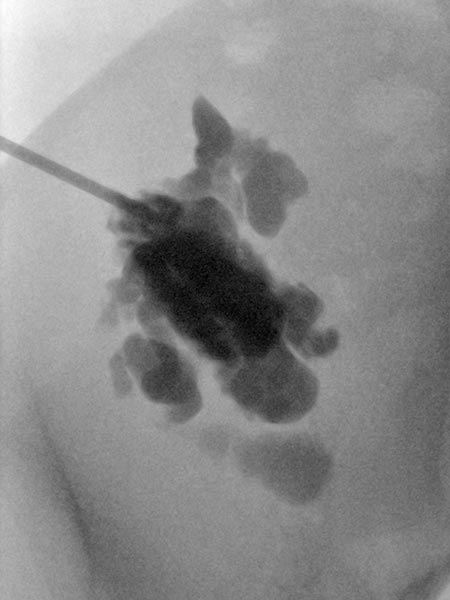

Ultrasound-guided puncture of the cystic portion of the LM during sclerotherapy. Via this puncture needle, the lymphatic malformation is first injected with contrast, then aspirated and the sclerosing agent is introduced.

Overview X-ray in the area of the right pelvic crest after injection of contrast medium via the needle directly located in the lymphatic malformation. Large parts of the lymphatic malformation are contrasted from this needle position, representing an optimal needle position for sclerotherapy.